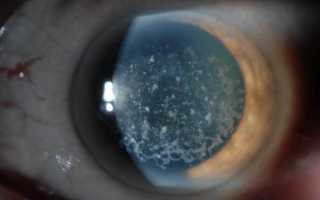

Макулярная (пятнистая) дистрофия роговицы. Имеет аутосомно-рецессивный тип наследования, ген CHST6 (сarbohydrate sulfotransferase 6 gene), локус 16q22. Морфологические изменения связаны с избыточным отложением в строме, эндотелии и десцеметовой мембране внутриклеточно и внеклеточно гликозаминогликанов. Заболевание проявляется в детском возрасте диффузным помутнением стромы, распространяющимся до лимба; позже обнаруживаются поверхностные центральные проминирующие неправильной формы белесые помутнения в виде пятен. В отличие от зернистой дистрофии, нет четких зон между помутнениями роговицы. В развитой стадии вовлекаются эндотелий и десцеметова мембрана, на которой обычно имеются каплевидные наложения — гутты. Позднее из-за эндотелиальной декомпенсации строма отекает и утолщается. К 20-30 годам острота зрения обычно значительно снижена, как и чувствительность роговицы, появляется светобоязнь. Из-за рецидивирующих эрозий возникают приступы боли.